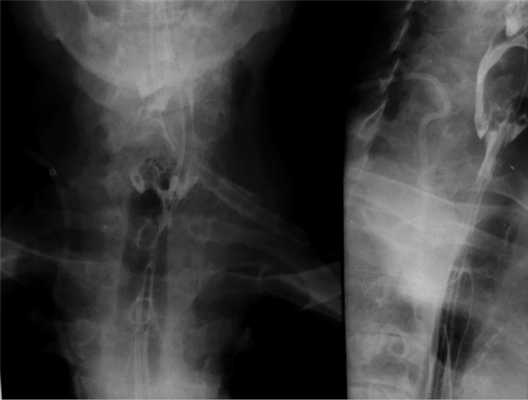

Таким образом, осуществлена трансаксиллярная эндовидеохирургическая безгазовая дивертикулэктомия. Дренирование и послойное ушивание раны. Продолжительность операции составила 137 мин: доступ — 35 мин, мобилизация дивертикула — 38 мин, интраоперационная эндоскопическая навигация и отсечение дивертикула — 25 мин, ушивание стенки пищевода и раны — 39 мин. Антибактериальный препарат ввели однократно в день операции. На 2-е сутки выполнили рентгенографию с водорастворимым контрастным препаратом. Признаков несостоятельности швов или сужения глоточно-пищеводного отдела нет (рис. 5). Дренаж удален (рис. 6). Пациенту разрешили пить, а с 3-х суток — принимать жидкую пищу. Клинических признаков повреждения возвратного гортанного нерва не отмечено. В удовлетворительном состоянии пациент выписан на 7-е сутки после операции. Осмотрен через 1 мес после вмешательства. Чувствует себя хорошо, жалоб не предъявлял, питался в полном объеме.

Рис. 5. Рентгенограммы пищевода (контрольное исследование). Отсутствие признаков деформации и сужения пищевода после операции.

а — прямая проекция; б — боковая проекция.